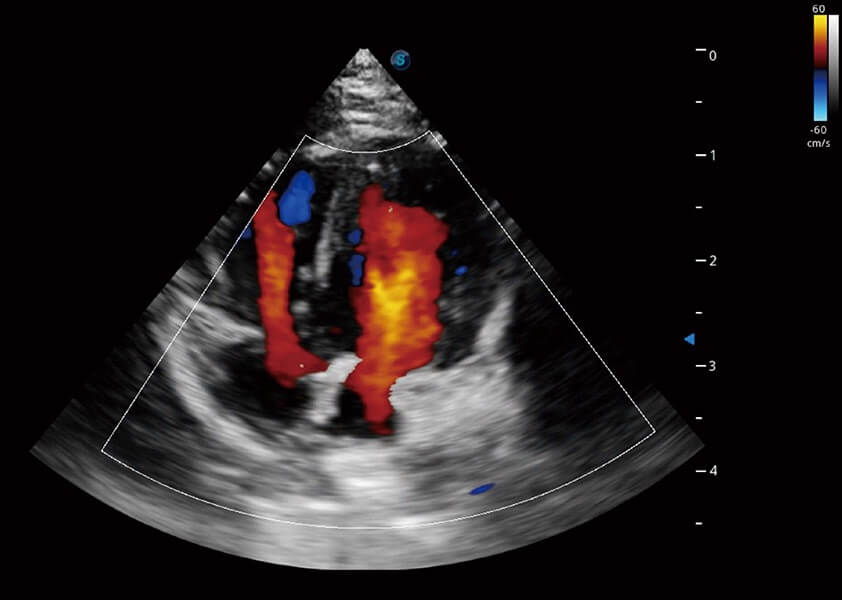

优异的基础图像

(犬)四腔心血流